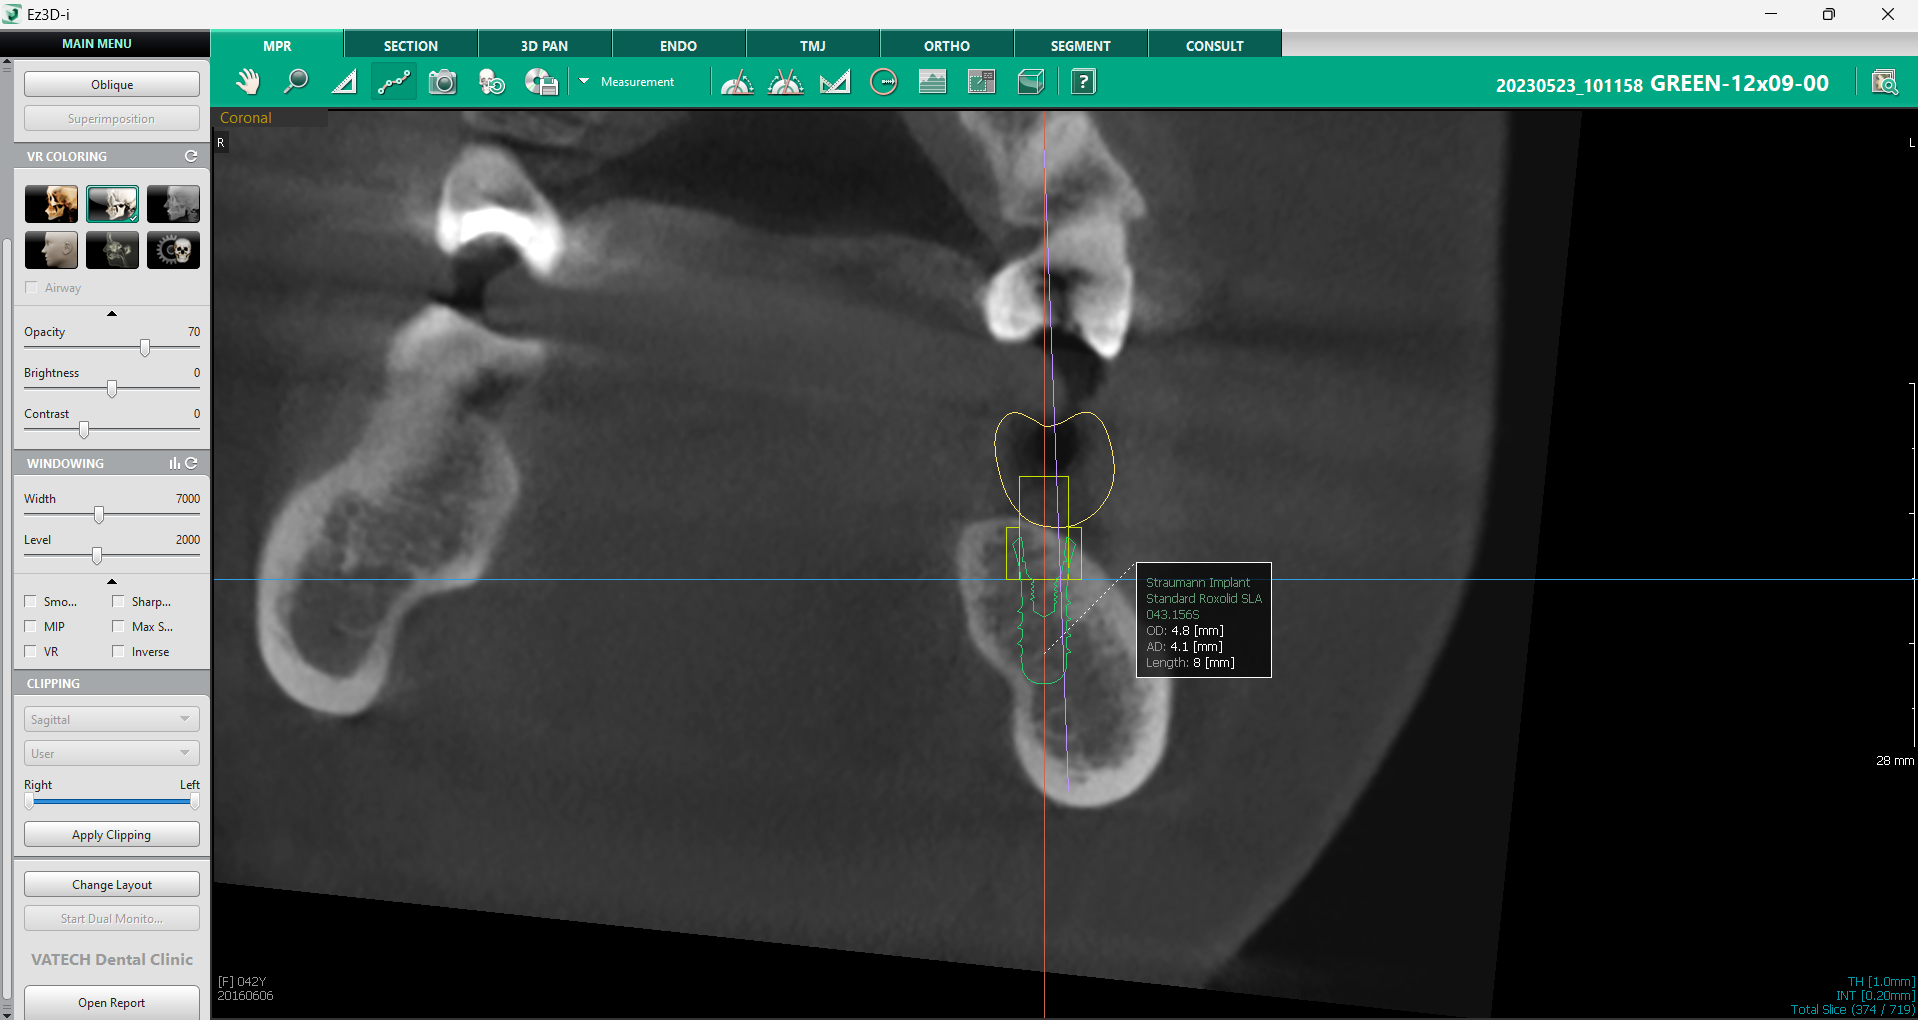

c. Informații despre implant

Un alt aspect crucial în procesul de verificare este accesul facil la toate informațiile relevante despre implant. Vizualizarea MPR oferă opțiunea de afișare detaliată a caracteristicilor implantului, facilitând organizarea și planificarea procedurii. Printr-un simplu click dreapta pe implant și selectarea opțiunii „Show Info”, se pot accesa toate detaliile esențiale, inclusiv tipul implantului, dimensiunea, linia de produse și alte specificații tehnice.

Această funcție este deosebit de utilă pentru coordonarea echipei medicale, deoarece permite o gestionare clară a fiecărui pas din procedură. Odată ce informațiile nu mai sunt necesare, ele pot fi ascunse rapid printr-un click nou pe implant și selectarea opțiunii „Hide Info”.